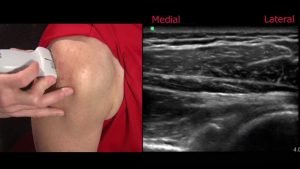

Ultrasound guided injections.

If you need an injection to help you recover from an injury, it will work better if it is put into the right place. We can use ultrasound to guide the needle into exactly the right place for the injection to be most beneficial. There is lots of evidence to show that when injections are performed without guidance they are less accurate. If the injection is not in the right place it is less likely to work. We use ultrasound for almost all our injections.